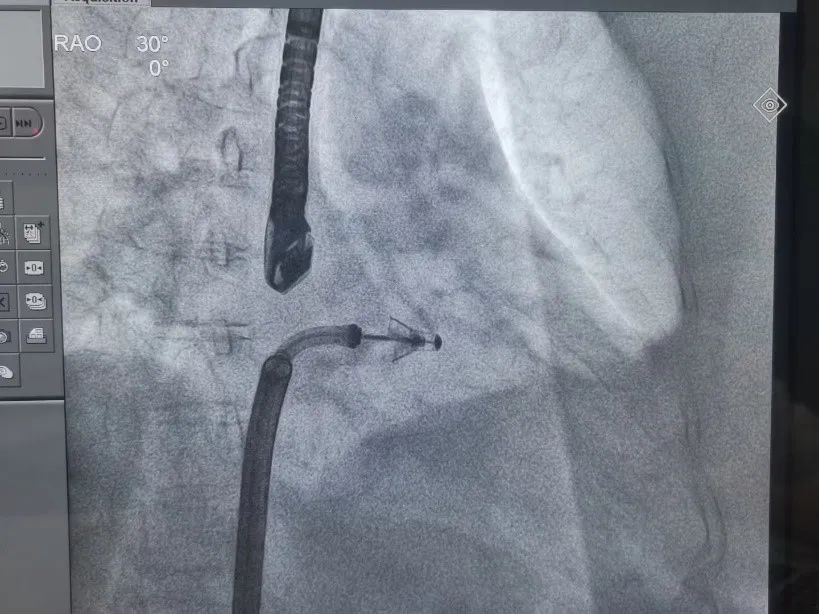

2021年8月27日,武汉大学人民医院江洪教授、陈静教授及超声科周青教授与浙江大学附属第二医院王建安教授团队密切合作,应用中国第一款自主研发的DragonFly经导管二尖瓣瓣膜夹系统,成功为一位高龄患者完成了经导管二尖瓣缘对缘修复手术。期间与美国弗吉尼亚大学医学中心David Scott Lim教授团队及香港亚心医院林逸贤教授全程视频连线沟通,团队通力合作,为患者早日康复尽心竭力。